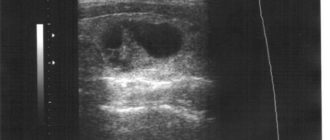

Что делать если обнаружили аденому надпочечника

Симптомы аденомы надпочечника: первые признаки и диагностика Аденома – это доброкачественная опухоль надпочечников. Данное